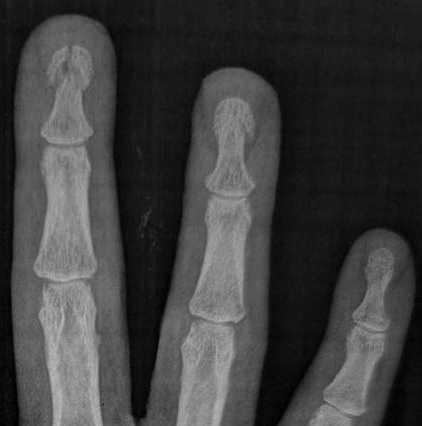

Ammar Haouimi, Radiopaedia.org. From the case rID: 86319

P3

- Si fracture de la houppe phalangienne distale : syndactylie + Cs CMF à 1 mois

- Si fracture proximale : avis chirurgical

P1 / P2

- Attelle plâtrée

- Avis chirurgical (si en garde la nuit : prévenir l’interne de CMF qui le verra à la consultation du lendemain).